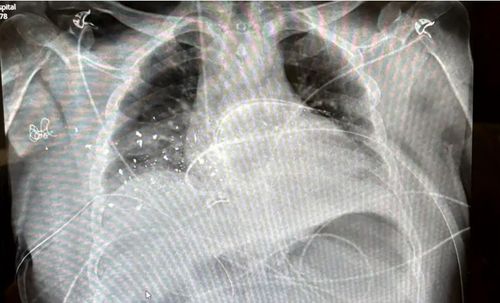

Rabbi Yanky Super's chest x-ray

He was shot in the chest and back, which left his body peppered with bullet fragments. (9News)

He sustained gunshot wounds to his chest and back, leaving his body embedded with bullet fragments.